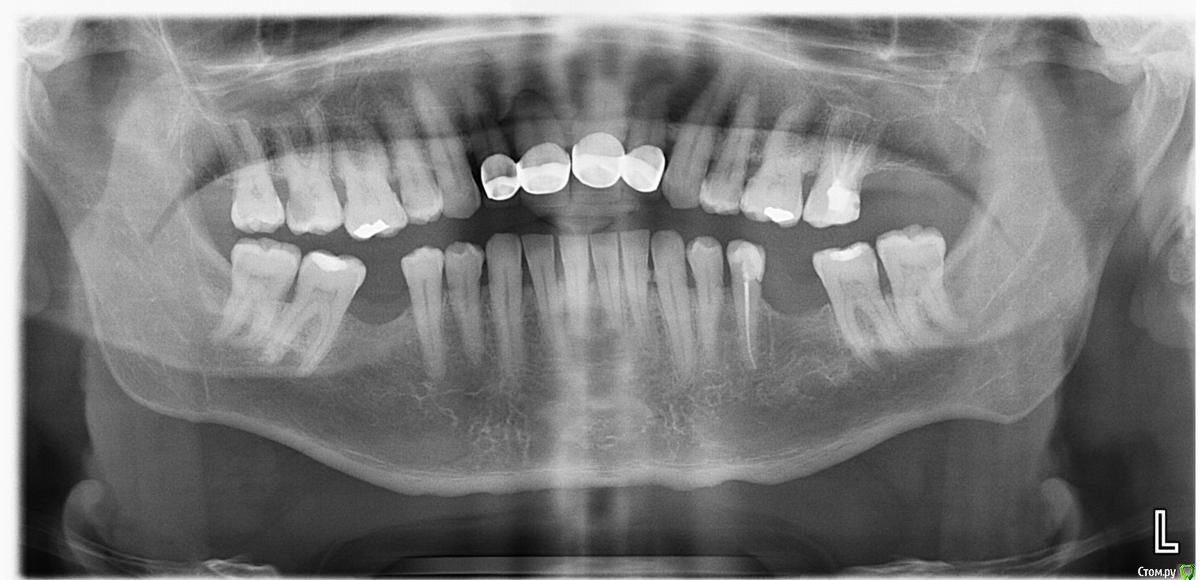

Дмитрий Л. Опубликовано 21 ноября, 2018 Поделиться Опубликовано 21 ноября, 2018 Коллеги, вот такая вот ситуация. Зубы 1 ст. подвижности. Планирую закрытый кюретаж... Как шинировать зубы, если они покрыты МК коронками? Сами коронки удовлетворительные, пациенту нравятся. Переделка коронок пародонтит здесь уже не вылечит. Но шинировать то надо . Какие варианты? Возможно, циркониевая шина? Может быть сошлифовать нёбно и в коффере протравить плавиковой, затем стекловолоконная композитная? Всё осложняется необходимостью провести лечение в минимум этапов, присутствует осложнённая соматика, каждое вмешательство требует аб терапии. Не знаю даже, на сколько успешным может быть кюретаж, 11 по большому счёту просится на удаление, но всё-таки хотелось бы миниинвазивно для начала всё сделать. Всем заранее спасибо) Ссылка на комментарий

Corsag21 Опубликовано 27 ноября, 2018 Поделиться Опубликовано 27 ноября, 2018 Модели бы хотелось посмотреть, подвижны только зубы 11, 12, 21, 22? Ссылка на комментарий

Жандос Муратович Опубликовано 27 ноября, 2018 Поделиться Опубликовано 27 ноября, 2018 11 по большому счёту просится на удаление ну раз проситься удаляйте) 1ст подвижности мммм нет скорее 12 держит 11) снимите 11,12они вроде раздельные от 21,22 .а там я думаю все и решиться) удачи Ссылка на комментарий